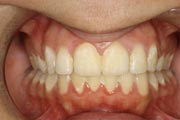

Crowding

Before